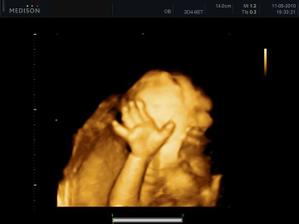

11.05. - (26+5) dnes jedeme na video

video se povedlo, máme asi 6 cca 5 - 10ti vteřinových videíí.Bylo to super. Karolínka se zase mlela jako drak. Je taková živoučká 😀

kontrola - vše v pořádku a máme + 8kg